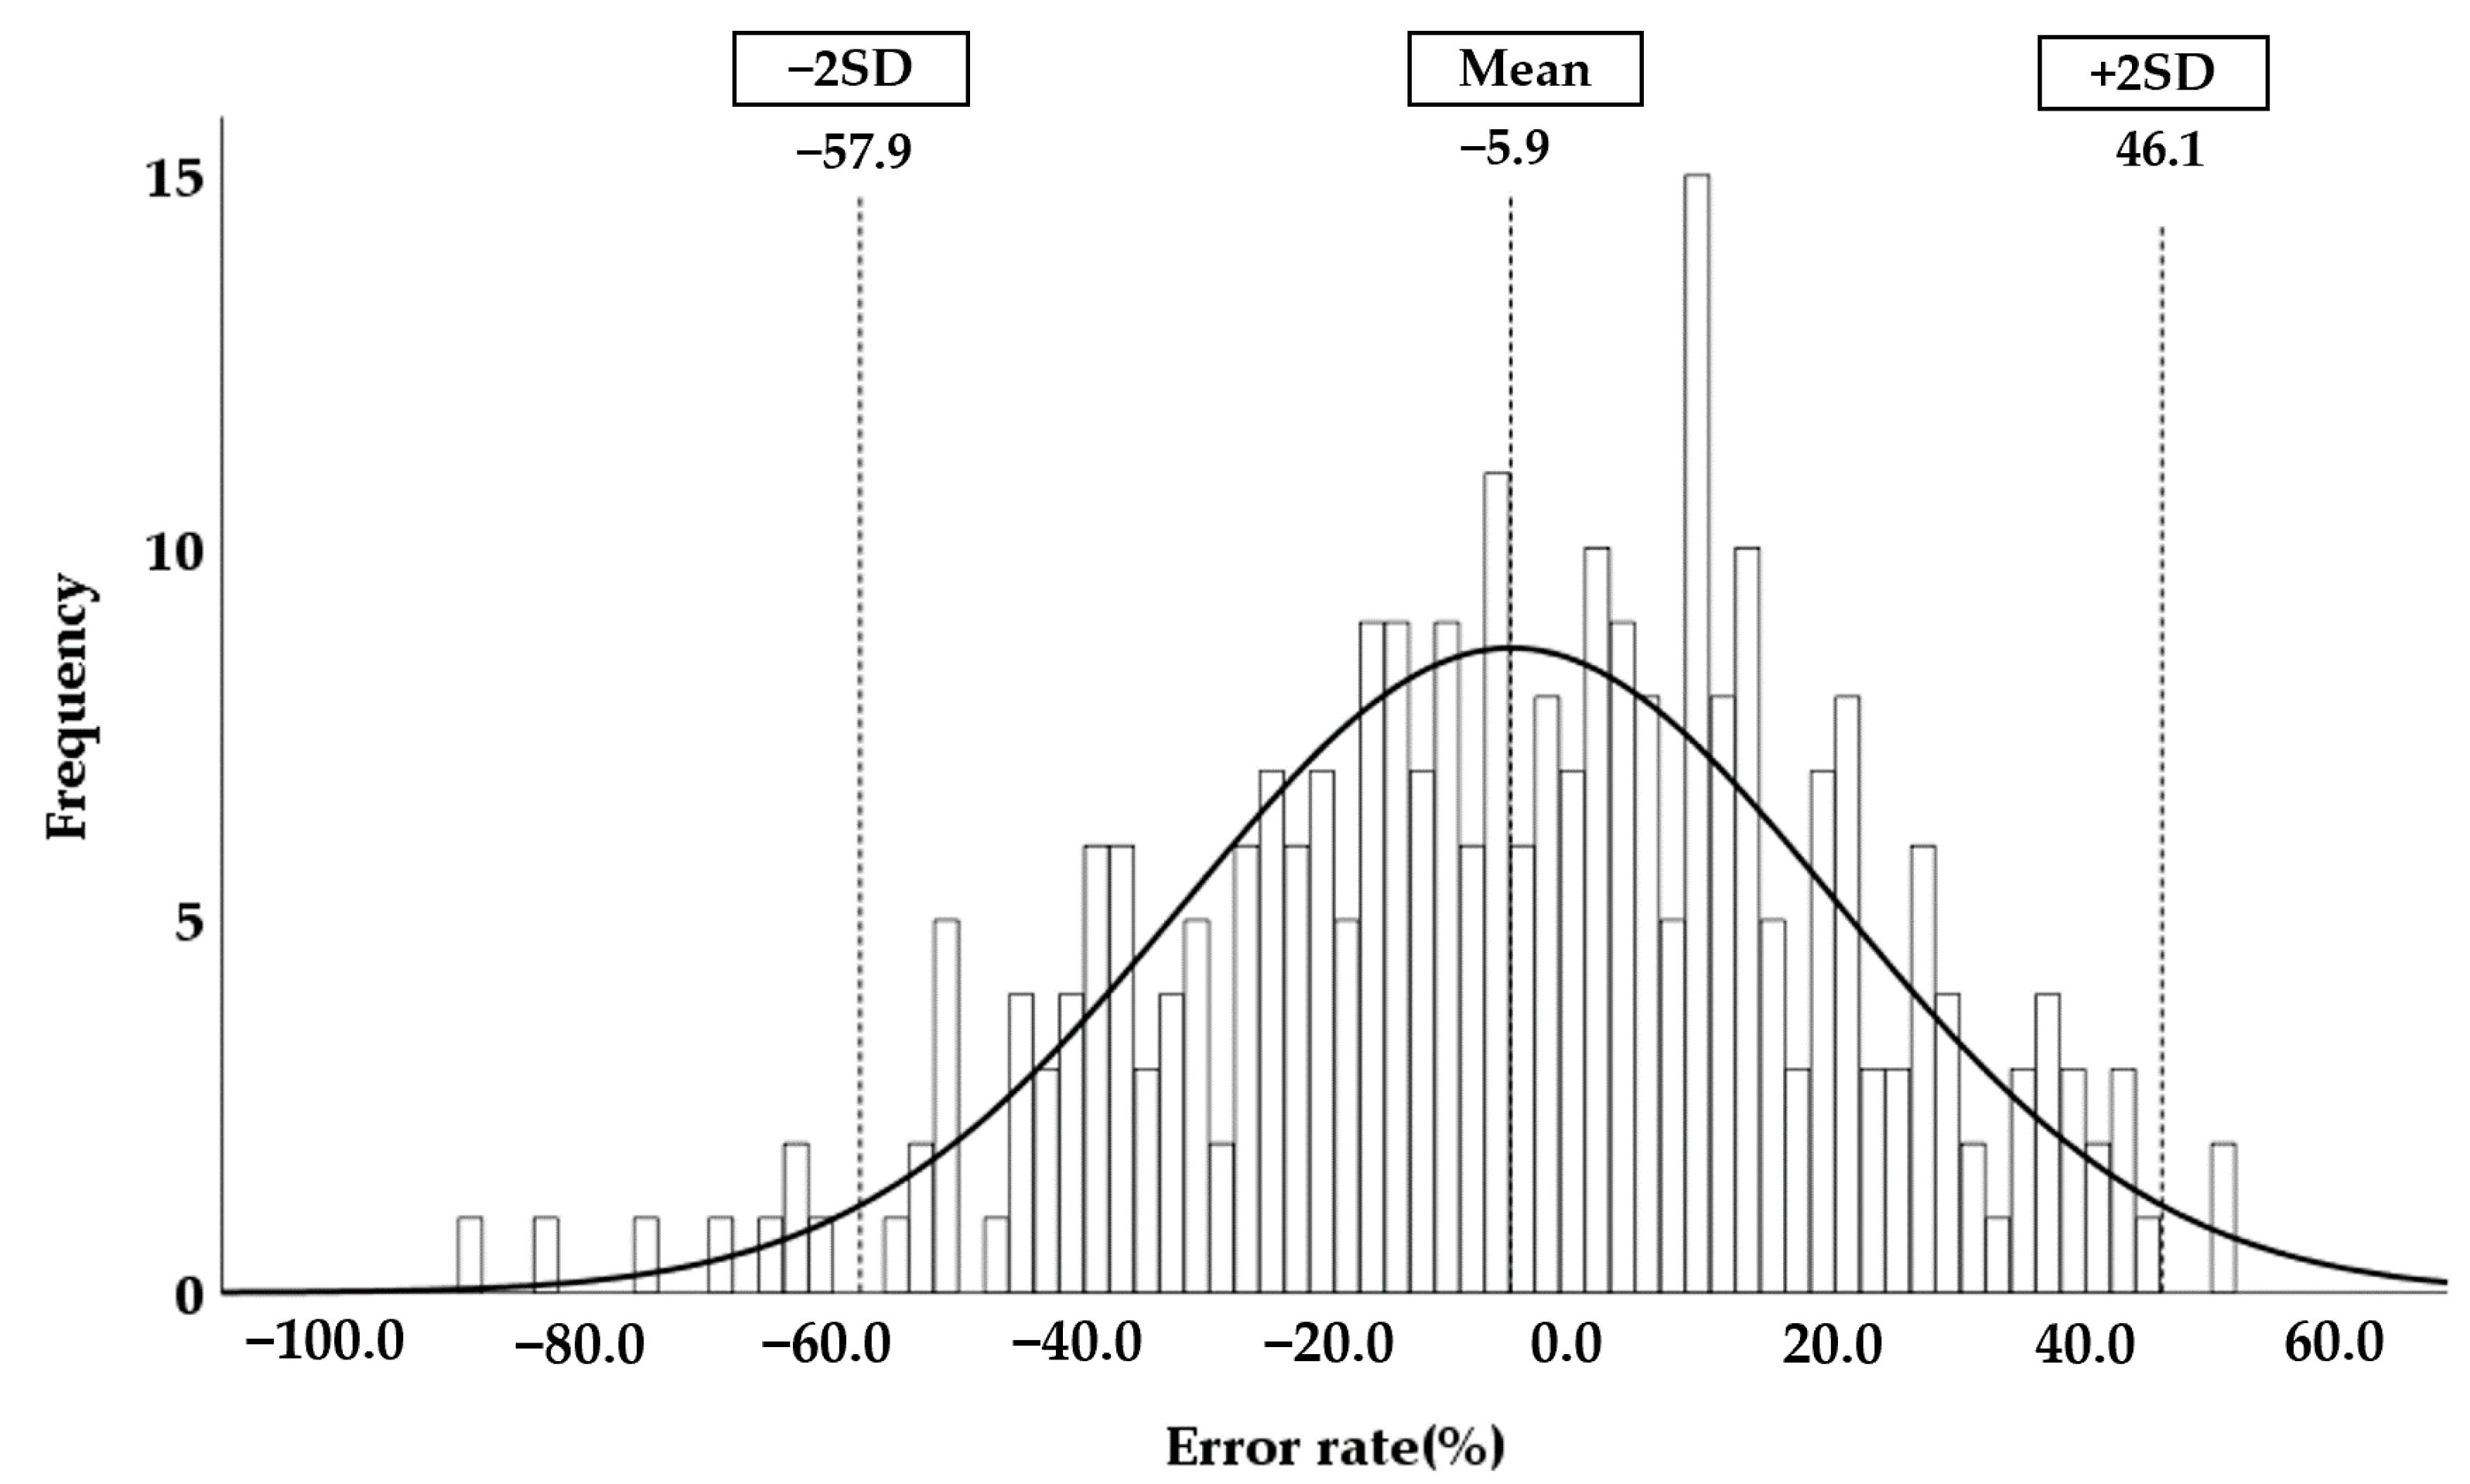

3.5. Accuracy of the Automatically Measured Kidney Volume Using Hybrid Learning